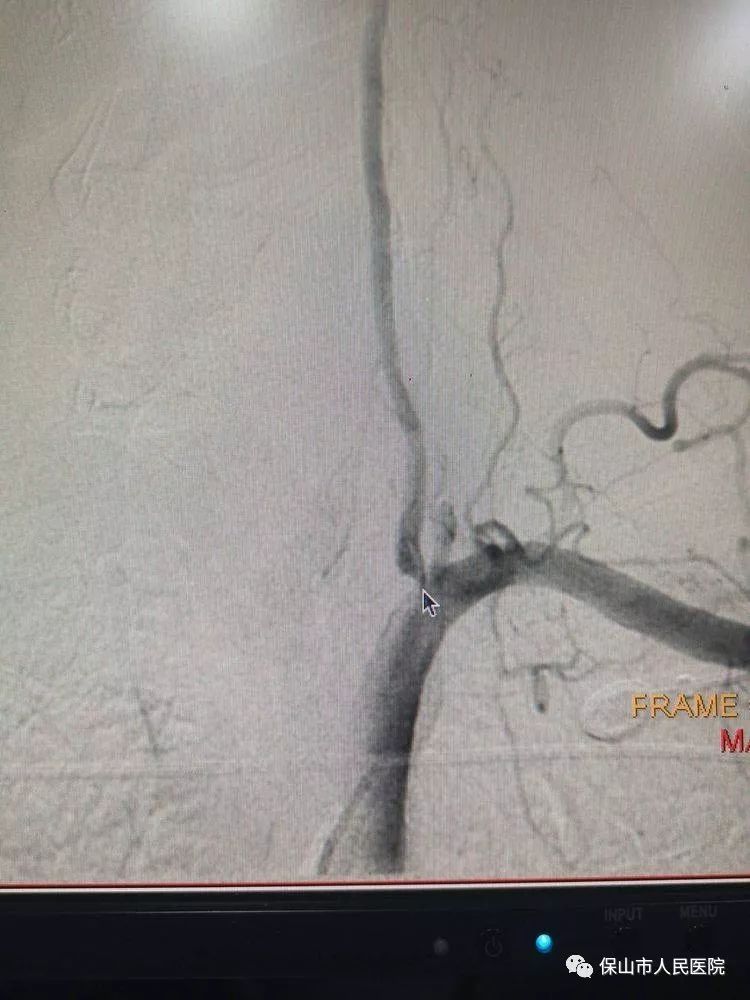

圖中箭頭指示的地方就是狹窄部位。左側(ce) 椎動脈於(yu) 開口處狹窄,狹窄程度在90%以上。

這樣左右對比更直觀,右側(ce) 椎動脈開口是正常的,術中造影證實左側(ce) 椎動脈開口重度狹窄,與(yu) 術前診斷一致。正是這個(ge) 狹窄,導致患者左側(ce) 椎動脈內(nei) 血流速度較慢,一定程度上影響了供血,所以患者才會(hui) 出現短暫性意識模糊和反複頭暈的症狀,因此,必須將狹窄部位重新開通。